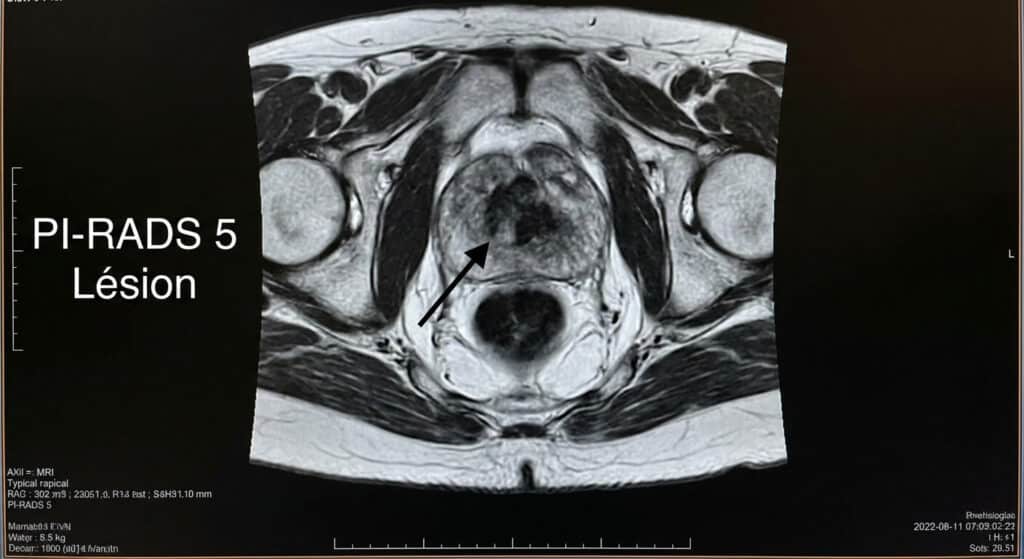

Le diagnostic du cancer de la prostate a été révolutionné par l’imagerie par résonance magnétique (IRM) multiparamétrique. Lors de cet examen, le radiologue utilise le score PI-RADS (Prostate Imaging-Reporting and Data System) pour évaluer le risque de malignité. Recevoir un résultat classé PI-RADS 5 pour la prostate signifie qu’une lésion présente une probabilité très élevée d’être un cancer cliniquement significatif.

Le score PI-RADS va de 1 (risque très faible) à 5 (risque très élevé). Une lésion classée PI-RADS 5 est généralement une masse de plus de 1,5 cm ou une lésion présentant des signes d’extension hors de la capsule prostatique. Visuellement, le radiologue observe une restriction de la diffusion des molécules d’eau et une prise de contraste rapide du produit de contraste, signes typiques des cellules cancéreuses denses et vascularisées.